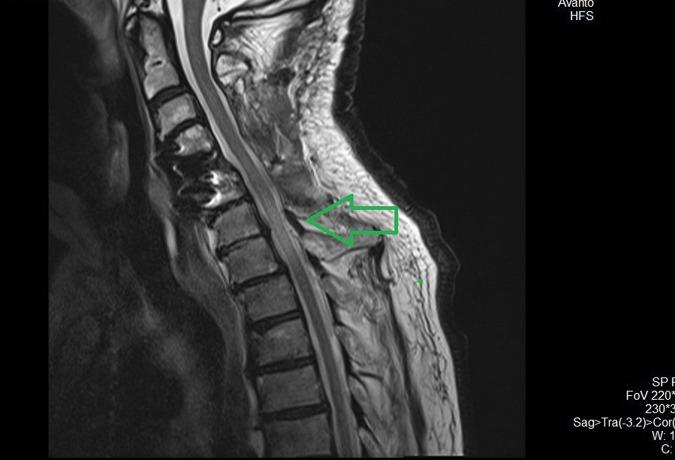

A 79-year-old male patient with Nurick grade 3 CSM was referred to our institution. He had already had a double-level C4-C6 anterior cervical decompression and fusion (ACDF) 2 years ago in another institution. The patient underwent posterior decompression from C3 to C6 plus C2-C7 lateral mass screw fusion. Within the first 24 h following surgery, he gradually developed C6 incomplete paraplegia (ASIA B). Cervical MRI disclosed a hypertensive signal in T2-weighted sequences at C6-C7 levels and the diagnosis of WCS was suspected. Revision surgery was made 30 h following our first surgery, with wider posterior decompression accompanied by intravenous methylprednisolone. The patient's neurologic status was improved, but the final neurologic outcome was worse (Nurick 4) than the preoperative status and subsequently did not change at all.

一名79岁、Nurick 3级颈椎病脊髓型颈椎病(CSM)男性患者被转诊至我院。他两年前在另一家机构已接受过C4 - C6双节段颈椎前路减压融合术(ACDF)。该患者接受了C3至C6后路减压及C2 - C7侧块螺钉融合术。术后最初24小时内,他逐渐发展为C6不完全性截瘫(美国脊髓损伤协会[ASIA] B级)。颈椎MRI显示C6 - C7水平T2加权序列有高信号,怀疑为WCS。在我们首次手术后30小时进行了翻修手术,进行了更广泛的后路减压并静脉注射甲泼尼龙。患者的神经状态有所改善,但最终神经功能结果比术前更差(Nurick 4级),且随后完全没有变化。